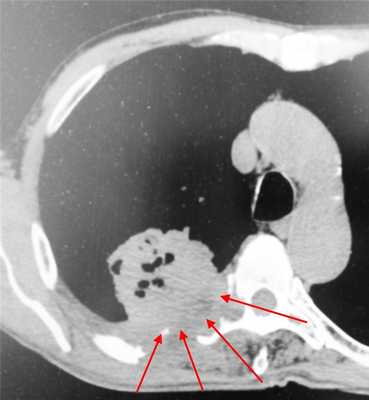

КТ-признаки центрального рака легкого: при компьютерной томографии определяется объемное образование мягкотканной структуры, в котором «обрывается» просвет нижнедолевого бронха. Края образования бугристые, неровные, со спикулами, форма неправильная.

Центральный рак легкого на КТ. Обратите внимание на различия в ширине просвета центральных бронхов справа и слева. Просвет правого верхнедолевого бронха не виден. Виден ателектаз верхней доли. В круге - непосредственно само опухолевое образование, ставшее причиной ателектаза.

Пример рака легких 4 стадии. Не показано оперативное лечение, только химиотерапия. Имеет место прорастание в ребра и позвоночник, а также в мягкие ткани грудной стенки. В строме опухоли видны множественные гиподенсные (темные) участки, содержащие газ - зоны распада.